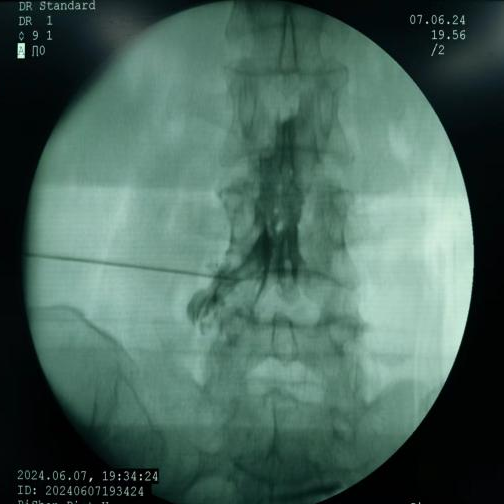

椎間盤射頻消融術(shù)、膠原酶椎間盤化學(xué)消融術(shù):兩種都是治療椎間盤突出癥的微創(chuàng)介入技術(shù)。射頻消融通過高頻電流汽化部分髓核,膠原酶則是通過化學(xué)酶溶解髓核,均能降低椎間盤壓力,從而解除神經(jīng)壓迫。

椎間盤射頻消融術(shù)、膠原酶椎間盤化學(xué)消融術(shù)